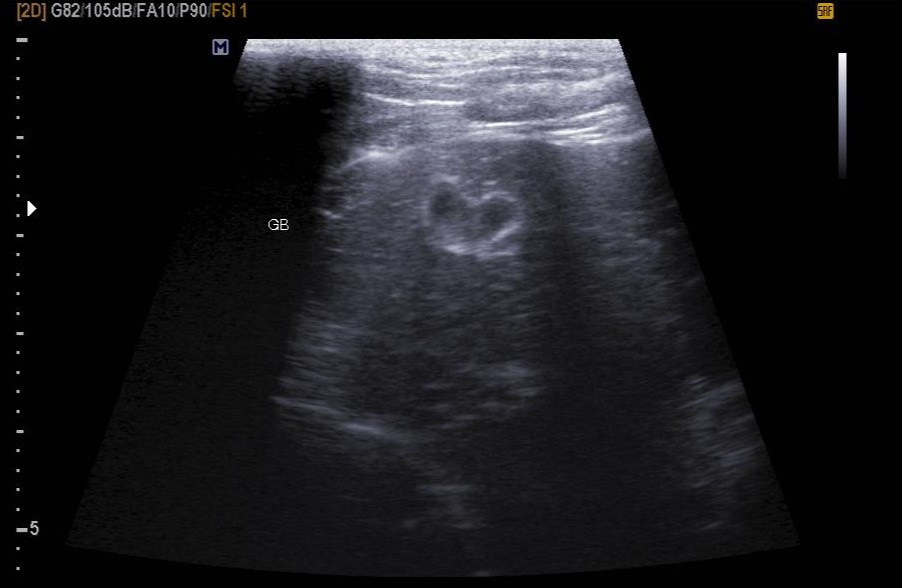

KakaoTalk_20230802_225343209.jpg 이아가 첫 항암주사를 맞기 전 촬영한 담낭 초음파. 보통 고양이 담낭은 동그란 모양인데, 가끔씩 이렇게 찌그러져 있는 경우가 있다고 한다. 심지어 귀여운 하트라니!

항암주사를 맞기에 앞서 체중과 체온, 심박수와 호흡수 등 기본적인 신체검사를 진행한다. 혈액검사를 통해 혈구 수치를 파악하고, 전해질 농도도 확인한다. 첫 항암이라 흉복부 방사선 검사와 신장, 비장 초음파도 진행했다. 이아의 경우 비강에 림프종이 생겼기 때문에, 혹시 다른 기관으로 전이됐는지를 확인하기 위해 이 같은 검사를 진행하게 됐다. (결과는 아직까진 럭키)